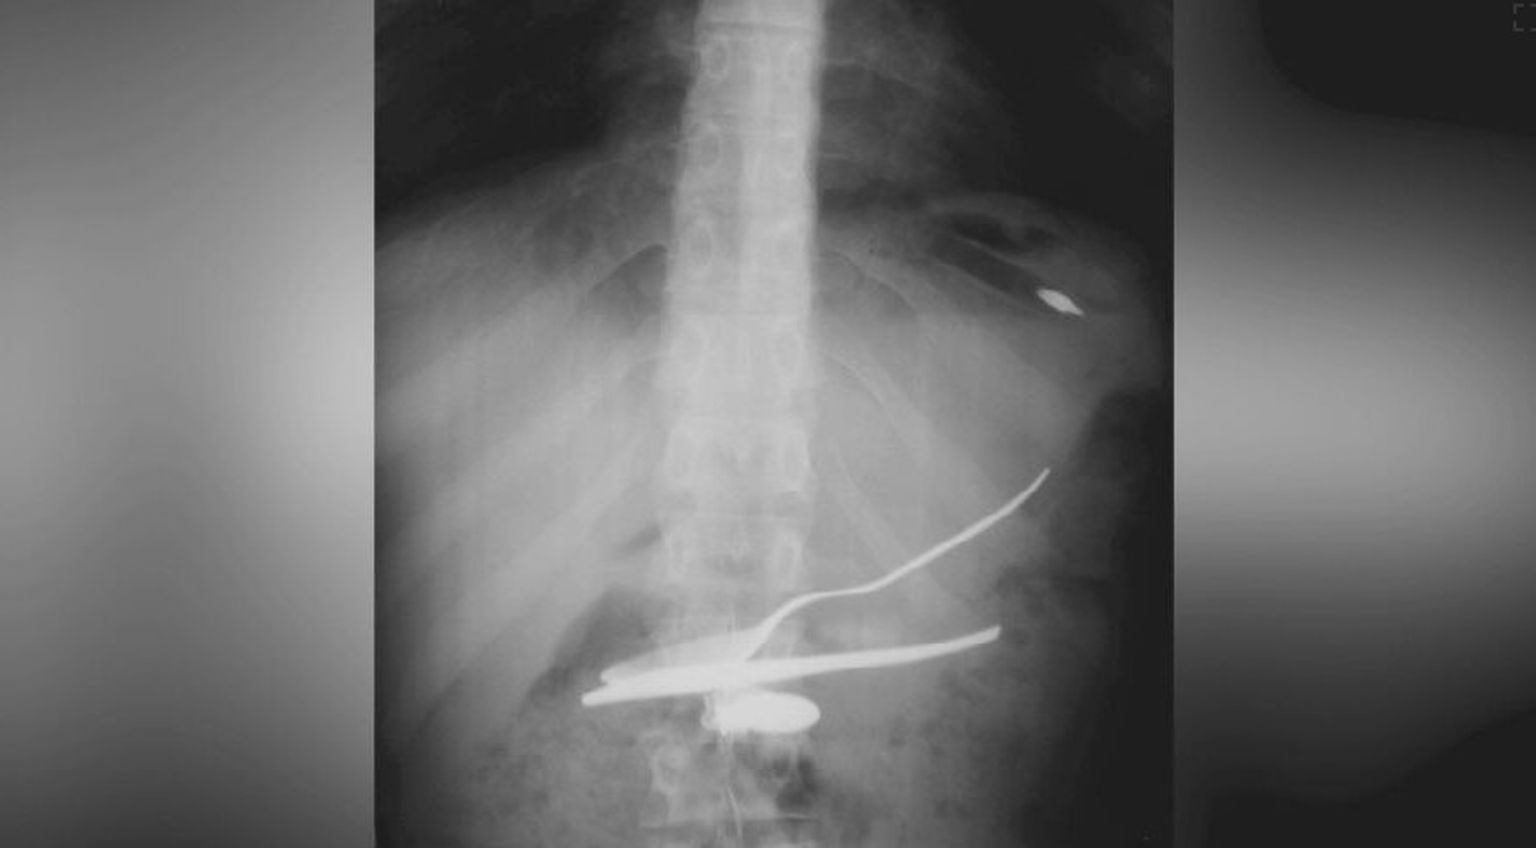

• Strano tijelo u tijelu, ilustracija - 1 Foto: DNEVNIK.hr

• Strano tijelo u tijelu, ilustracija - 2 Foto: DNEVNIK.hr

• Strano tijelo u tijelu, ilustracija - 3 Foto: DNEVNIK.hr

• Strano tijelo u tijelu, ilustracija - 4 Foto: DNEVNIK.hr

• Strano tijelo u tijelu, ilustracija - 5 Foto: DNEVNIK.hr